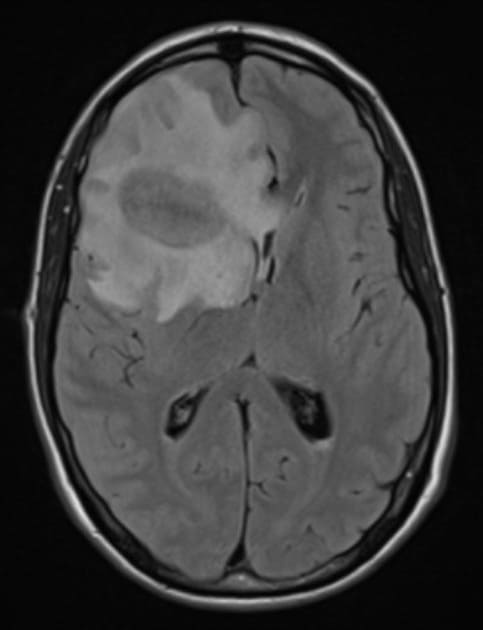

Apxe não

» Thông tin: Nam giới – 35 tuổi.

» Lâm sàng: Đau đầu.